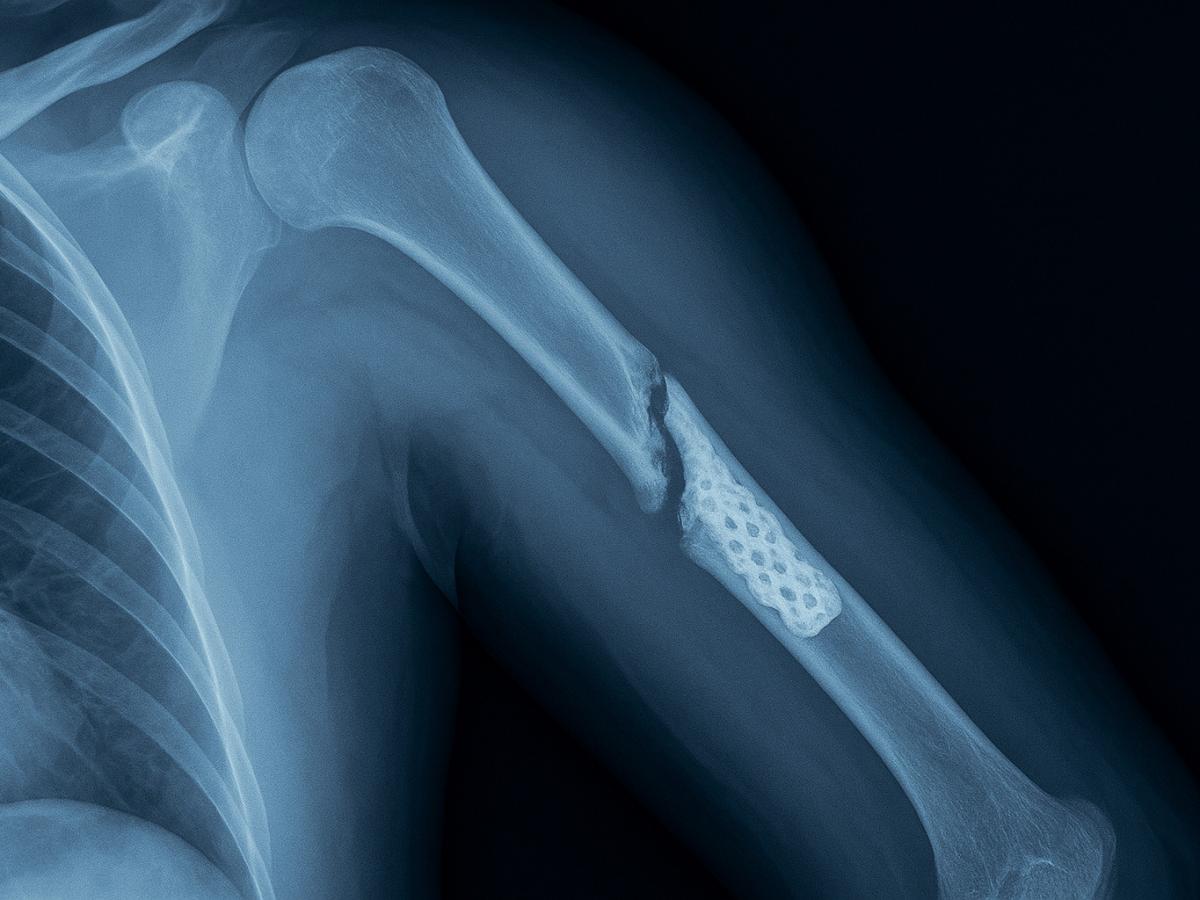

Рентген с 3D-имплантатом

Зима приносит не только красоту, но и опасность — лёд под ногами становится причиной множества травм. В гололёд достаточно одного неловкого шага, чтобы оказаться на земле. По словам хирурга Игоря Клочихина, чаще всего при падении страдают шейка бедра и лучевая кость — это тяжёлые переломы, требующие длительного восстановления. Однако многие повреждения можно предотвратить или облегчить, если знать, как правильно действовать.

"Наиболее распространённые травмы при падении на льду — это переломы шейки бедра и лучевой кости. Они часто вызывают ограничение подвижности и серьёзные осложнения", — отметил хирург Игорь Клочихин.